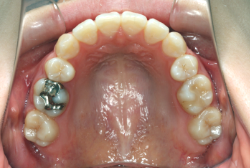

「左奥歯でものが噛めない」という主訴で来院したケースです。診断の結果、基本的には「叢生」という隙間が足りないと言うことが原因の凸凹症例でしたが、左下の乳歯が高校生になってもまだ残存している状態で、そのせいで噛み合わせが極端に悪くなっていました。

検査の結果、乳歯の下には後継ぎの永久歯が先天的に欠如していました。配列の凸凹が厳しく非抜歯で矯正することは難しく、仮に無理をして非抜歯治療をしても後々「後戻り」が懸念されることから、このような症例の場合は通常、上下顎左右第一小臼歯を抜歯させていただくのですが、左下は乳歯を抜歯して、第一小臼歯は残すことにしました。これで結果として、小臼歯部を上下左右で一つずつ減らしたのと同じ状況になります。治療後は歯並びが綺麗になっただけでなく、噛み合わせ的にも正しい状態が確立しています。

このように、先天的に永久歯が足りないという症例は最近増えています。親知らずはなくても特に問題になりませんが、その他の歯が足りないと言うのは審美的にも機能的にも重大な障害となります。しかし、矯正治療を正しく行えば、結果として歯がすべてあった場合と全く同じ仕上げにすることも可能です。